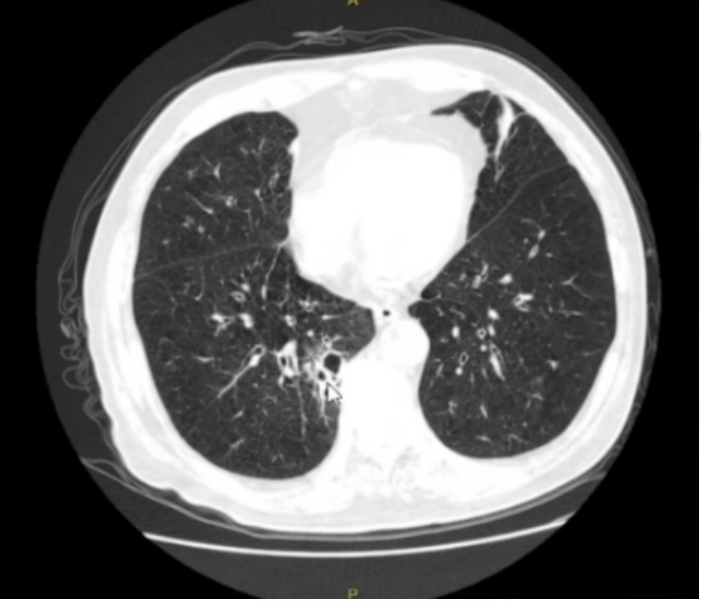

• 胸部CT(2022-08-07):两肺多发结节样高密度影,部分伴空洞,感染性病灶可能,肿瘤性病灶可能,建议进步诊治;两肺多发炎症、渗出;肺气肿,慢性支气管炎;纵隔内多发肿大淋巴结;两侧胸膜增厚(图1)

图片

1  患者胸部CT(2022-08-07)